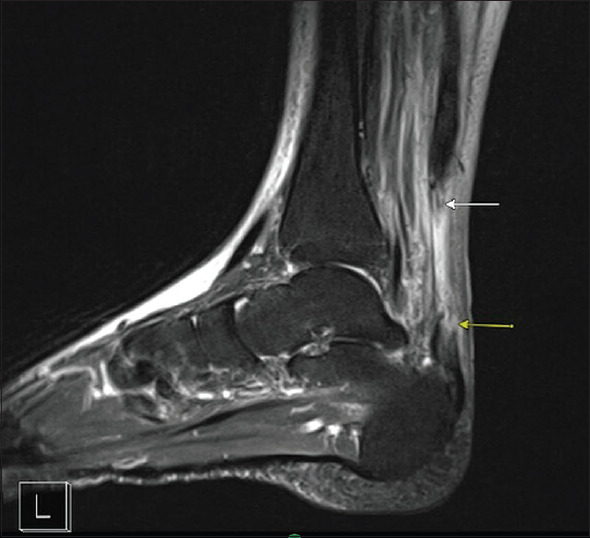

Stingray injuries, though common in coastal regions, rarely result in severe musculoskeletal complications such as tendon rupture. This case report presents the first documented instance of a 61-year-old male who sustained a stingray injury to the Achilles tendon, initially masked by a concurrent infection, leading to a delayed diagnosis and surgical repair. The patient presented to urgent care 5 days postinjury with pain, erythema, and chills, and was treated for a soft-tissue infection. Persistent symptoms prompted a referral to the emergency department (ED), where magnetic resonance imaging revealed a complete Achilles tendon rupture with associated infection. Surgical repair was delayed until the infection resolved, and a V-Y gastrocnemius advancement was performed 9 weeks postinjury. The patient achieved full recovery at 1-year follow-up. This case underscores the importance of a high index of suspicion for musculoskeletal injuries in marine trauma, the role of advanced imaging in the ED, and the need for interdisciplinary management to prevent long-term complications. Emergency physicians must consider tendon injuries in patients with persistent symptoms following stingray envenomation, ensuring timely diagnosis and treatment to optimize outcomes.